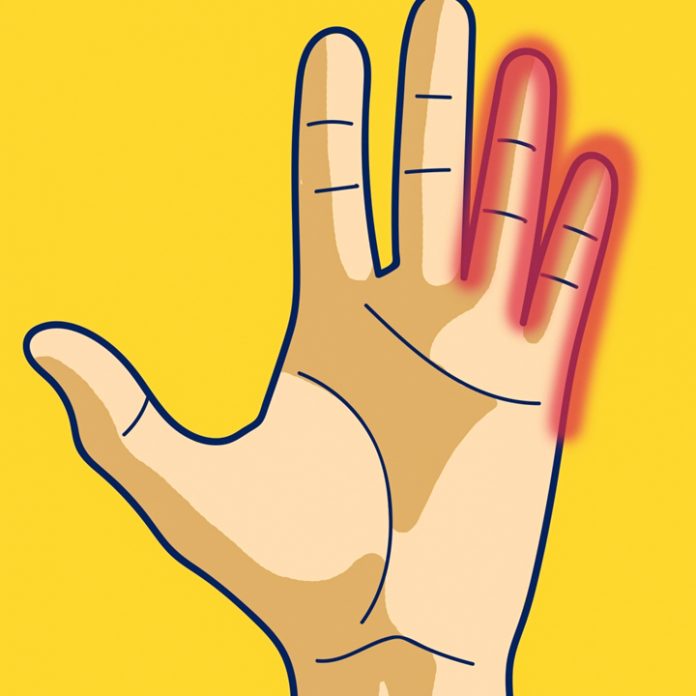

Слідкуйте за своїми долонями! 7 хвороб, про які попереджають наші руки

Якби ми частіше слухали своє тіло, то могли б уникнути 80% захворювань. Сьогодні ми розповімо, що можуть розповісти руки про ваш стан здоров’я? Пошкодження хребта може викликати проблеми з нервовими […]